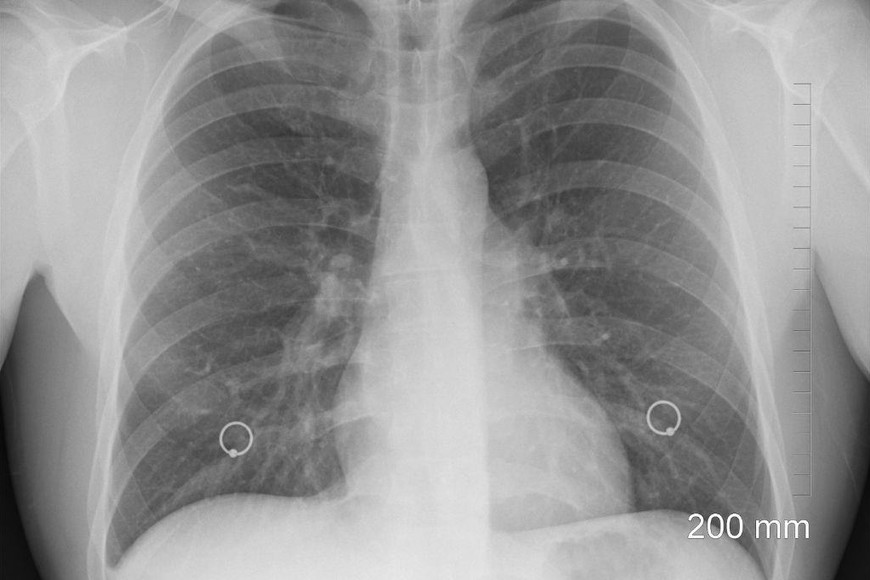

El cáncer de pulmón es el tumor más prevalente y agresivo, se estima que se producen anualmente unos dos millones de nuevos diagnósticos a nivel global. En la Argentina, según cifras del Instituto Nacional del Cáncer, se registran unos 12 mil nuevos casos por año. En tanto, de acuerdo al último Boletín de Estadísticas Vitales del Ministerio de Salud de la Nación, esta enfermedad fue responsable de 9.300 fallecimientos en 2019, una cifra muy cercana a la mortalidad conjunta de los cánceres de mama y de próstata.

Si bien muchas veces el cáncer de pulmón recién se diagnostica en estados avanzados, algunos síntomas a los que habría que estar atentos son tos persistente o que empeora, dolor de pecho, dificultades para respirar, sibilancias, tos con sangre, sensación de cansancio permanente y pérdida de peso sin una causa conocida.

Según las estimaciones realizadas por la Agencia Internacional de Investigación sobre Cáncer a partir de los datos obtenidos de registros poblacionales de nuestro país, se detectan por año más de 12.110 casos nuevos de cáncer de pulmón en Argentina, de los cuales se calcula que un 85% pertenece al cáncer de pulmón de tipo células no pequeñas y, entre estos, un 65% aproximado corresponde a estadios avanzados.